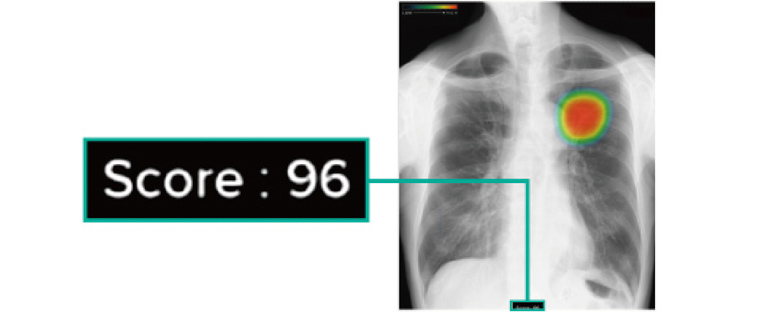

0~100に分けられた確信度スコアの最大値が数値として表示されます。

胸部レントゲン所見のスコア値は、数値が高いほど「治療が必要かもしれない病変」の可能性が高くなります。そのため、スコア値が高い場合には胸部CTによる詳しい検査を受けていただくことがあります。

胸部レントゲンAI診断システムは現在、富士フイルム社を含め数社から提供されています。ただし、富士フイルム社のAI診断システムCXR-AID以外のシステムにはスコア値測定機能がありません。スコア値測定機能は、1回の検査による精密精査の必要性だけでなく、経過観察によるスコア値の変化による検査の必要性の判断も可能になり、早期発見につながります。